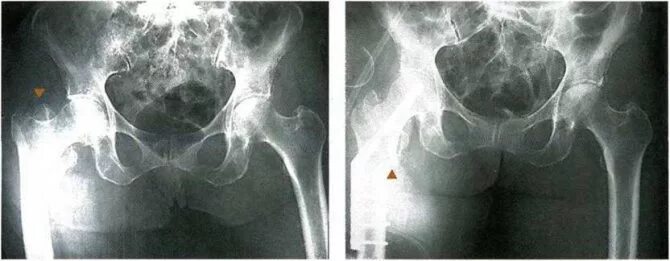

Снимок костей как называется